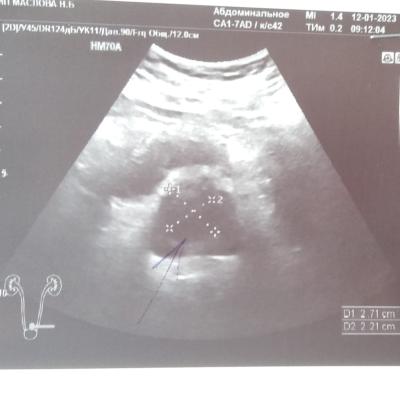

Здравствуйте.Сдал анализ ПСА,пришёл результат 12,свободный 0,8.остальные анализы кровь моча в норме.боли не беспокоют,сделали узи.результат прикрепляю.что это может быть.заранее спасибо!

Добрый день! Нужно выполнить МРТ малого таза, если в простате будут обнаружены подозрительные участки - нужно делать биопсию. В Барнауле можете обратиться к профессору Неймарку Борису Александровичу. Удачи.